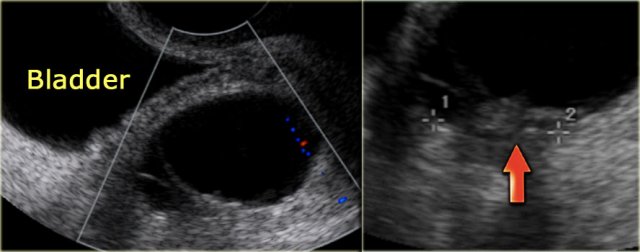

The transvaginal ultrasound images show a small complex ovarian cyst with wall vascularity on power Doppler analysis.

The characteristic circular Doppler appearance is called the 'ring of fire'.

Note, there is good through-transmission and no internal vascularity, consistent with a, partially involuted, corpus luteum cyst.

Another case with the typical the 'ring of fire' on ultrasound.